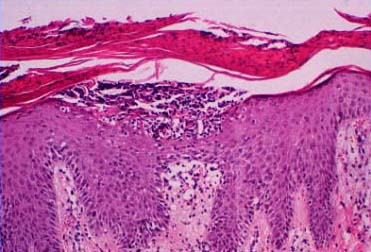

The earliest pinhead-sized macules or smooth-surfaced papules show subtle histologic changes with a preponderance of dermal changes . At first, there is capillary dilation and edema in the papillary dermis, with a lymphocytic infiltrate surrounding the capillaries. The lymphocytes extend to the lower portion of the epidermis, where slight spongiosis develops. Then focal changes occur in the upper portion of the epidermis, where granular cells become vacuolated and disappear, and mounds of parakeratosis are formed. Neutrophils are usually seen only at the summits of some of the mounds of parakeratosis and appear scattered through an otherwise orthokeratotic cornified layer . These mounds of parakeratosis with neutrophils represent the earliest manifestation of Munro microabscesses . At this stage, which is characterized clinically by an early scaling papule, a histologic diagnosis of psoriasis can often be made. In some cases, when there is marked |

exocytosis of neutrophils, they may aggregate in the uppermost portion of the spinous layer to form small spongiform pustules of Kogoj. Lymphocytes remain confined to the lower epidermis, which, as more and more mitoses occur, becomes increasingly hyperplastic. The epidermal changes are at first focal, but later become confluent, leading clinically to plaques. In the fully developed lesions of psoriasis, as best seen at the margin of enlarging plaques, the histologic picture is characterized by (a) acanthosis with regular elongation of the rete ridges with thickening in their lower portion; (b) thinning of the suprapapillary epidermis with the occasional presence of small spongiform pustules; (c) pallor of the upper layers of the epidermis; (d) diminished to absent granular layer; (e) confluent parakeratosis; (f) the presence of Munro microabscesses; (g) elongation and edema of the dermal papillae; and (h) dilated and tortuous capillaries . |

The suprapapillary epidermis appears relatively thin in comparison with the markedly elongated rete ridges, and the cells in the upper layers of the epidermis may appear enlarged and pale stained as a result of intracellular edema and hypogranulosis. Keratinocytes beneath the parakeratotic cornified layer may be intermingled with neutrophils . The histologic picture is then that of a small spongiform pustule of Kogoj . Although it is only a micropustule, it is nevertheless of the same type as the much larger macropustules seen in pustular psoriasis. Such a spongiform pustule, highly diagnostic for psoriasis and its variants, shows aggregates of neutrophils within the interstices of a spongelike network formed by degenerated and thinned epidermal cells |

Guttate or eruptive psoriasis shows the histologic features of an early or active lesion of psoriasis, where there is more pronounced inflammatory infiltrate and less acanthosis as compared with a well-developed chronic plaque of psoriasis. Because of its acute onset, one may observe the remaining normal basket-weave orthokeratotic cornified layer overlying the mounds of parakeratosis with neutrophils, which, in turn, may appear loosely arranged . |